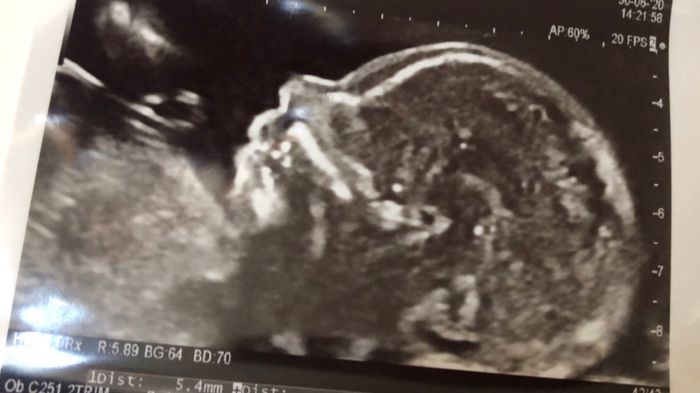

Future mamme novembre 2020 ๐ŸŒž๐Ÿ๐ŸŒทโ™พ

Da Lalla , Il 30 Giugno 2020 alle 15:22